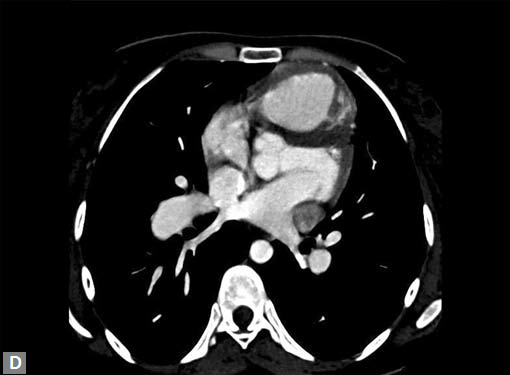

On occasions, thromboembolism can also be seen in right

ventricle and less commonly in pulmonary veins. Systemic

vein thrombus (innominate veins, SVC, IVC) sometimes

accompanies pulmonary thromboembolism (Figs 18A and B).

Right ventricular strain is picked up when RV/LV ratio is

more than one with deviation of interventricular septum to

left.